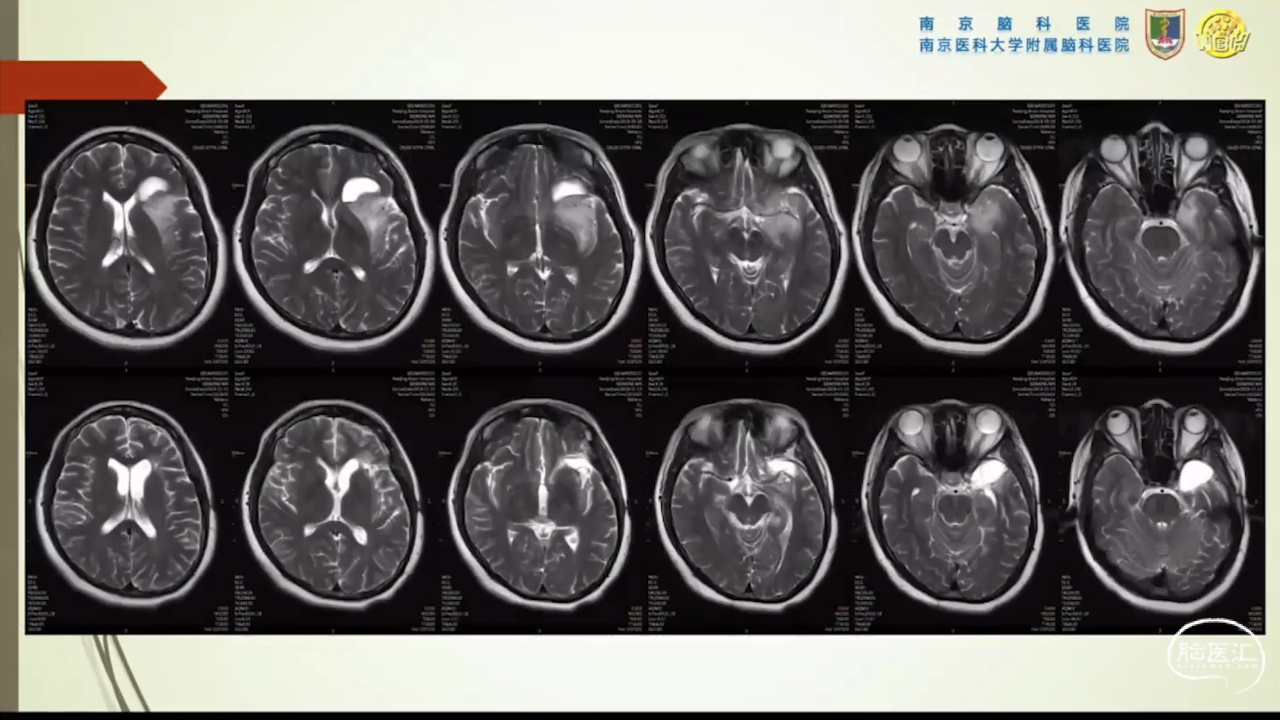

胶质瘤是发病率最高的颅内肿瘤(约占44.69%),岛叶是神经胶质瘤的好发部位,大约有25%的低级别胶质瘤及10%的高级别胶质瘤发生在岛叶,大多数岛叶胶质瘤为低级别胶质瘤。岛叶在调节内脏感觉运动、控制心血管交感活性、传入躯体感觉中均起重要作用。它也参与了痛觉的传递、运动规划、自主性吞咽、味觉、听觉、前庭功能、情绪、认知能力和语言能力。因为岛叶解剖结构复杂,并覆盖有高级语言皮层、白质束及重要的血管结构,故岛叶部位的手术难度极大。

讲题岛叶胶质瘤的显微手术治疗